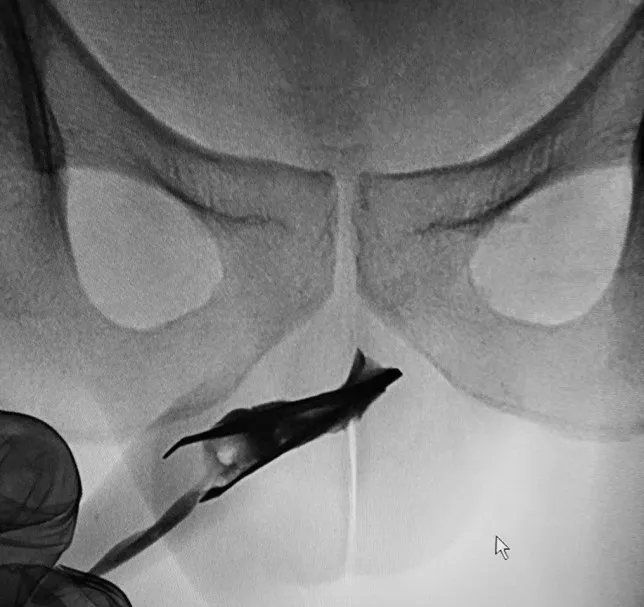

A 8 centiméter hosszú csipesz eltávolításának egy kisebb orvosgárda látott neki. A műtét nem volt könnyű, mivel a csipesz nyitott vége könnyen felsérthette volna belülről a beteg péniszét kihúzás közben. A körülményekre való tekintettel végül altatás mellett döntöttek az orvosok, nehogy a páciens hirtelen reakciói még nagyobb bajt okozzanak műtét közben. A beavatkozás annyira sikeres volt, hogy a beteget még aznap haza is engedték a kórházból.

Az orvostudományi feljegyzésekben alapján ez volt a második eset, amikor egy csipeszt kellett eltávolítani valakinek a húgycsövéből.